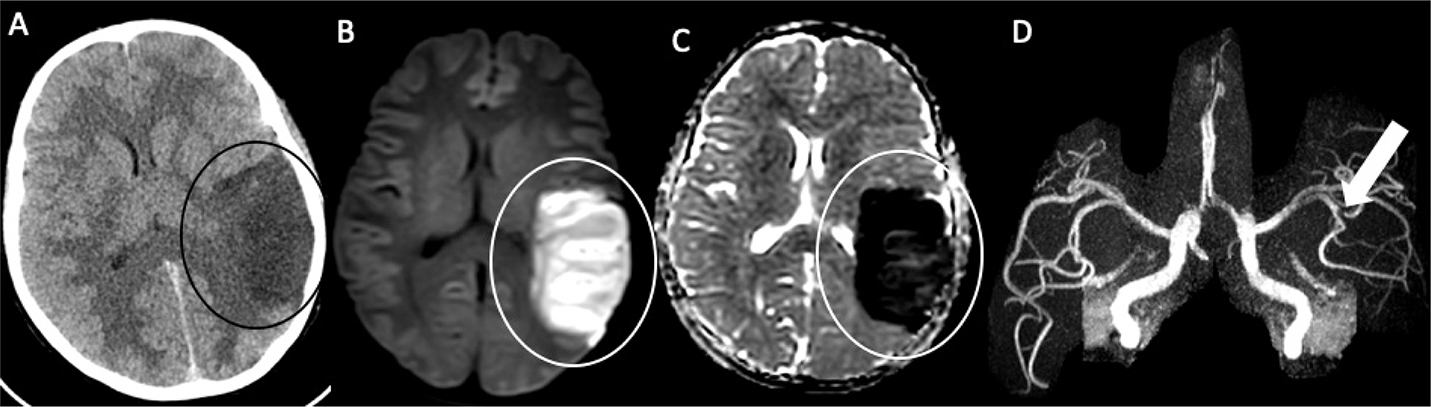

Fig 1

Figure 1. A six-month-old male who presented with acute right hemiparesis. DWI (A) demonstrates acute infarct in the left basal ganglia and deep white matter (white arrow). MRA (B) shows severe stenosis of the left M1 middle cerebral artery segment (black arrow). Follow-up 4 months later, demonstrates evolution of the infarct, now with encephalomalacia and gliosis without new acute infarct (white arrowhead) (C). MRA at that times shows mild improvement but persistent MCA stenosis (black arrowhead) (D). Findings are most compatible with focal cerebral arteriopathy.

Figure 4. A 19-year-old female with a history of Down syndrome and repaired ASD and VSD. The patient presented with 2 days of aphasia, alerted mental status, and right upper quadrant field cut. Axial CT (A) demonstrates hypoattenuation with loss of gray-white differentiation in the left middle cerebral artery territory (black circle). DWI (B) and corresponding ADC (C) confirm acute left MCA territory infarct (white circle). MRA (D) demonstrates focal left MCA M2/M3 occlusion (arrow). She was found to be positive for Lupus anticoagulant.